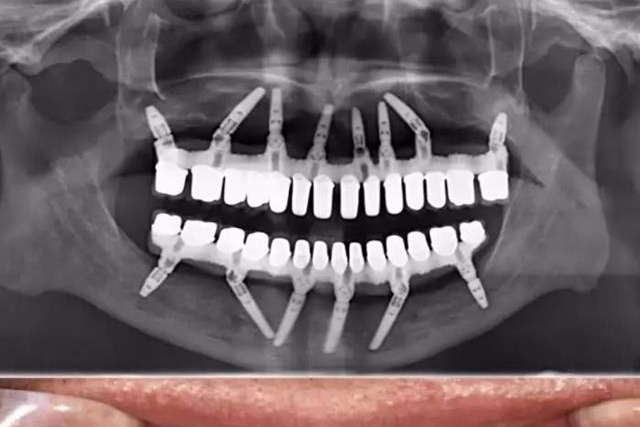

牙周炎,一个非恶性的相对缓和的健康杀手,它对国人健康施出的温柔一刀,虽不致命,却足以让大多数人后半生的生活质量遭遇滑铁卢,苦不堪言。如果早期牙周炎患者拒绝治疗和忽视口腔卫生管理,那么,最终“满口无牙”会是一个大概率事件。上图是一个30多岁的小伙子牙周炎的最终归宿——全口牙松动,拔除。在口腔大夫那里,这些病例已经司空见惯了,一句话形容:看起来,他们一颗牙也不缺,其实,已经一颗牙也不在了!正因为如此,...